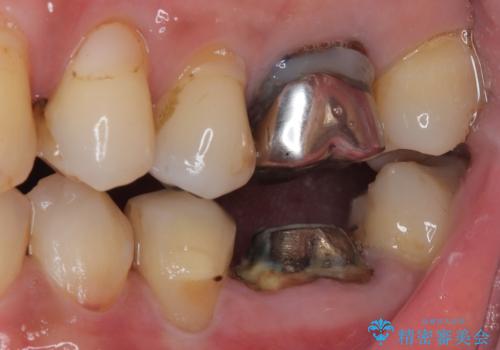

下顎大臼歯の抜歯即時埋入インプラント治療では、複数ある歯根のうち、後方の歯根部にインプラントを埋入することで一般的であり、今回破折して骨吸収が著しいのは前方の歯根であったため、事前に仮歯を用意した上で、抜歯即時埋入インプラントによる補綴治療を行うこととしました。

来院されるまではインプラント治療を躊躇されていましたが、抜歯即時埋入により、単回の外科処置で治療が終えられることのメリットを理解され、インプラントによる補綴治療を行いました。

スムーズに治療を終えることができました。